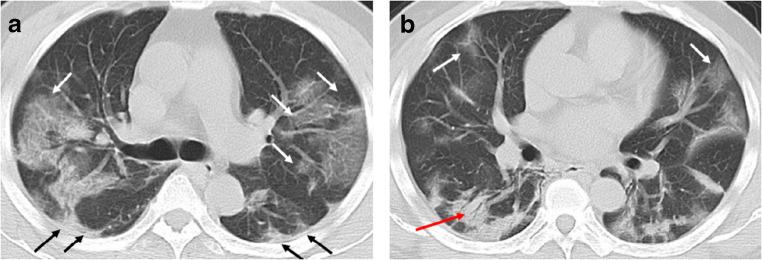

The majority of infected patients had a history of exposure in Wuhan or to infected patients and mostly presented with fever and cough. More than half of the patients presented bilateral, multifocal lung lesions, with peripheral distribution, and 53 (59%) patients had more than two lobes involved. Of all included patients, COVID-19 pneumonia presented with ground glass opacities in 65 (72%), consolidation in 12 (13%), crazy paving pattern in 11 (12%), interlobular thickening in 33 (37%), adjacent pleura thickening in 50 (56%), and linear opacities combined in 55 (61%). Pleural effusion, pericardial effusion, and lymphadenopathy were uncommon findings. In addition, baseline chest CT did not show any abnormalities in 21 patients (23%), but 3 patients presented bilateral ground glass opacities on the second CT after 3-4 days.

SARS-CoV-2 infection can be confirmed based on the patient's history, clinical manifestations, imaging characteristics, and laboratory tests. Chest CT examination plays an important role in the initial diagnosis of the novel coronavirus pneumonia. Multiple patchy ground glass opacities in bilateral multiple lobular with periphery distribution are typical chest CT imaging features of the COVID-19 pneumonia.

大多数感染患者有武汉接触史或感染患者接触史,主要表现为发热和咳嗽。超过一半的患者表现为双侧、多灶性肺部病变,呈外周分布,53 例(59%)患者有两个以上肺叶受累。所有纳入患者中,COVID-19 肺炎 65 例(72%)表现为磨玻璃影,12 例(13%)为实变,11 例(12%)为铺路石征,33 例(37%)为小叶间隔增厚,50 例(56%)为邻近胸膜增厚,55 例(61%)为线状混浊合并。胸腔积液、心包积液和淋巴结病少见。此外,21 例患者(23%)基线胸部 CT 无任何异常,但 3 例患者在第 3-4 天后第二次 CT 检查时出现双侧磨玻璃影。

根据患者的病史、临床表现、影像学特征和实验室检查可以确诊 SARS-CoV-2 感染。胸部 CT 检查在新型冠状病毒肺炎的初步诊断中起重要作用。双侧多发性肺叶多灶性分布的多发性斑片状磨玻璃影是 COVID-19 肺炎的典型胸部 CT 影像学特征。